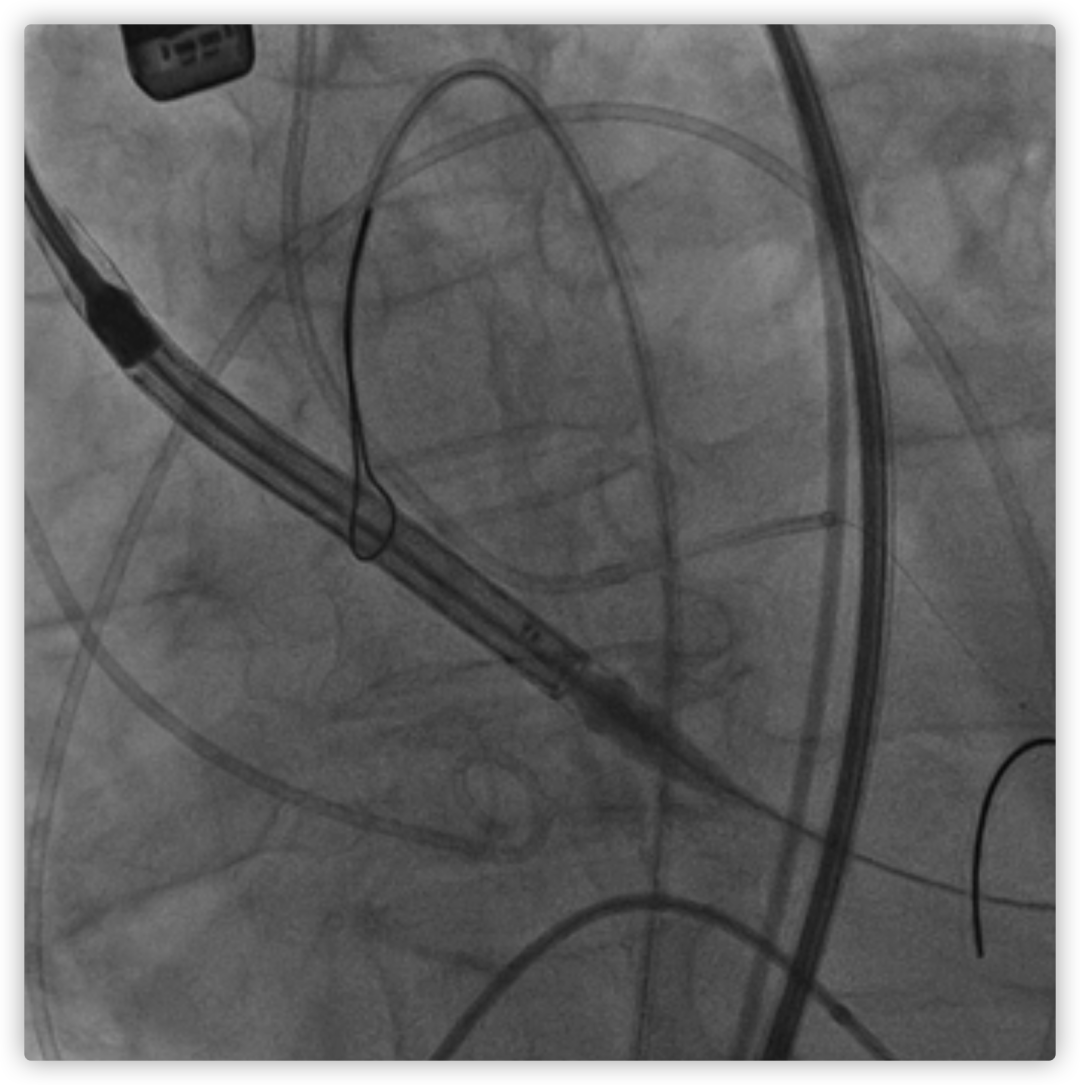

26VenusAplus+snare

瓣膜内22mm球囊后扩张,左冠无显影

LM烟囱支架植入4.0*30mm